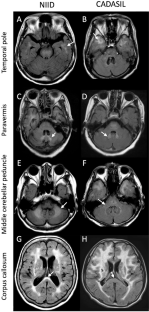

Neuronal intranuclear inclusion disease (NIID) is an autosomal dominant inherited neurodegenerative disease caused by NOTCH2NLC GGC repeat expansions. A high-intensity signal in the corticomedullary junction (CMJ) on magnetic resonance (MR) diffusion-weighted imaging (DWI) is a well-known characteristic of NIID. However, because of its diverse clinical symptoms and frequent presence of cerebral white matter hyperintensity (WMH) lesions on MRI, patients with NIID may be suspected of having other leukoencephalopathies. The aim of the present study was to identify patients with NOTCH2NLC GGC repeat expansions among those with undiagnosed leukoencephalopathies, recruited from NOTCH3-negative cerebral autosomal dominant arteriopathy with subcortical infarcts and leukoencephalopathy (CADASIL)-suspected and GFAP-negative Alexander disease (AxD)-suspected patients. Among 459 NOTCH3-negative CADASIL-suspected patients, 18 (3.9%) showed NOTCH2NLC GGC repeat expansions; however, among 40 GFAP-negative AxD-suspected patients, none exhibited such repeat expansions. On comparing 17 patients with GGC repeat expansions, whose clinical information was available, with 179 CADASIL probands previously reported by us, the former showed significantly higher frequencies of seizure (23.5 vs. 6.9%, respectively), WMH in the corpus callosum (92.9 vs. 9.2%, respectively), paravermis (21.4 vs. 2.7%, respectively), and middle cerebellar peduncle (21.4 vs. 3.4%, respectively), and DWI high-intensity signals in CMJ (61.5 vs. 1.4%, respectively). In conclusion, not only DWI high-intensity signals in CMJ, but also the WMH distribution, particularly a high frequency in the corpus callosum, and presence of seizures are useful for detecting NIID in patients with undiagnosed leukoencephalopathies.